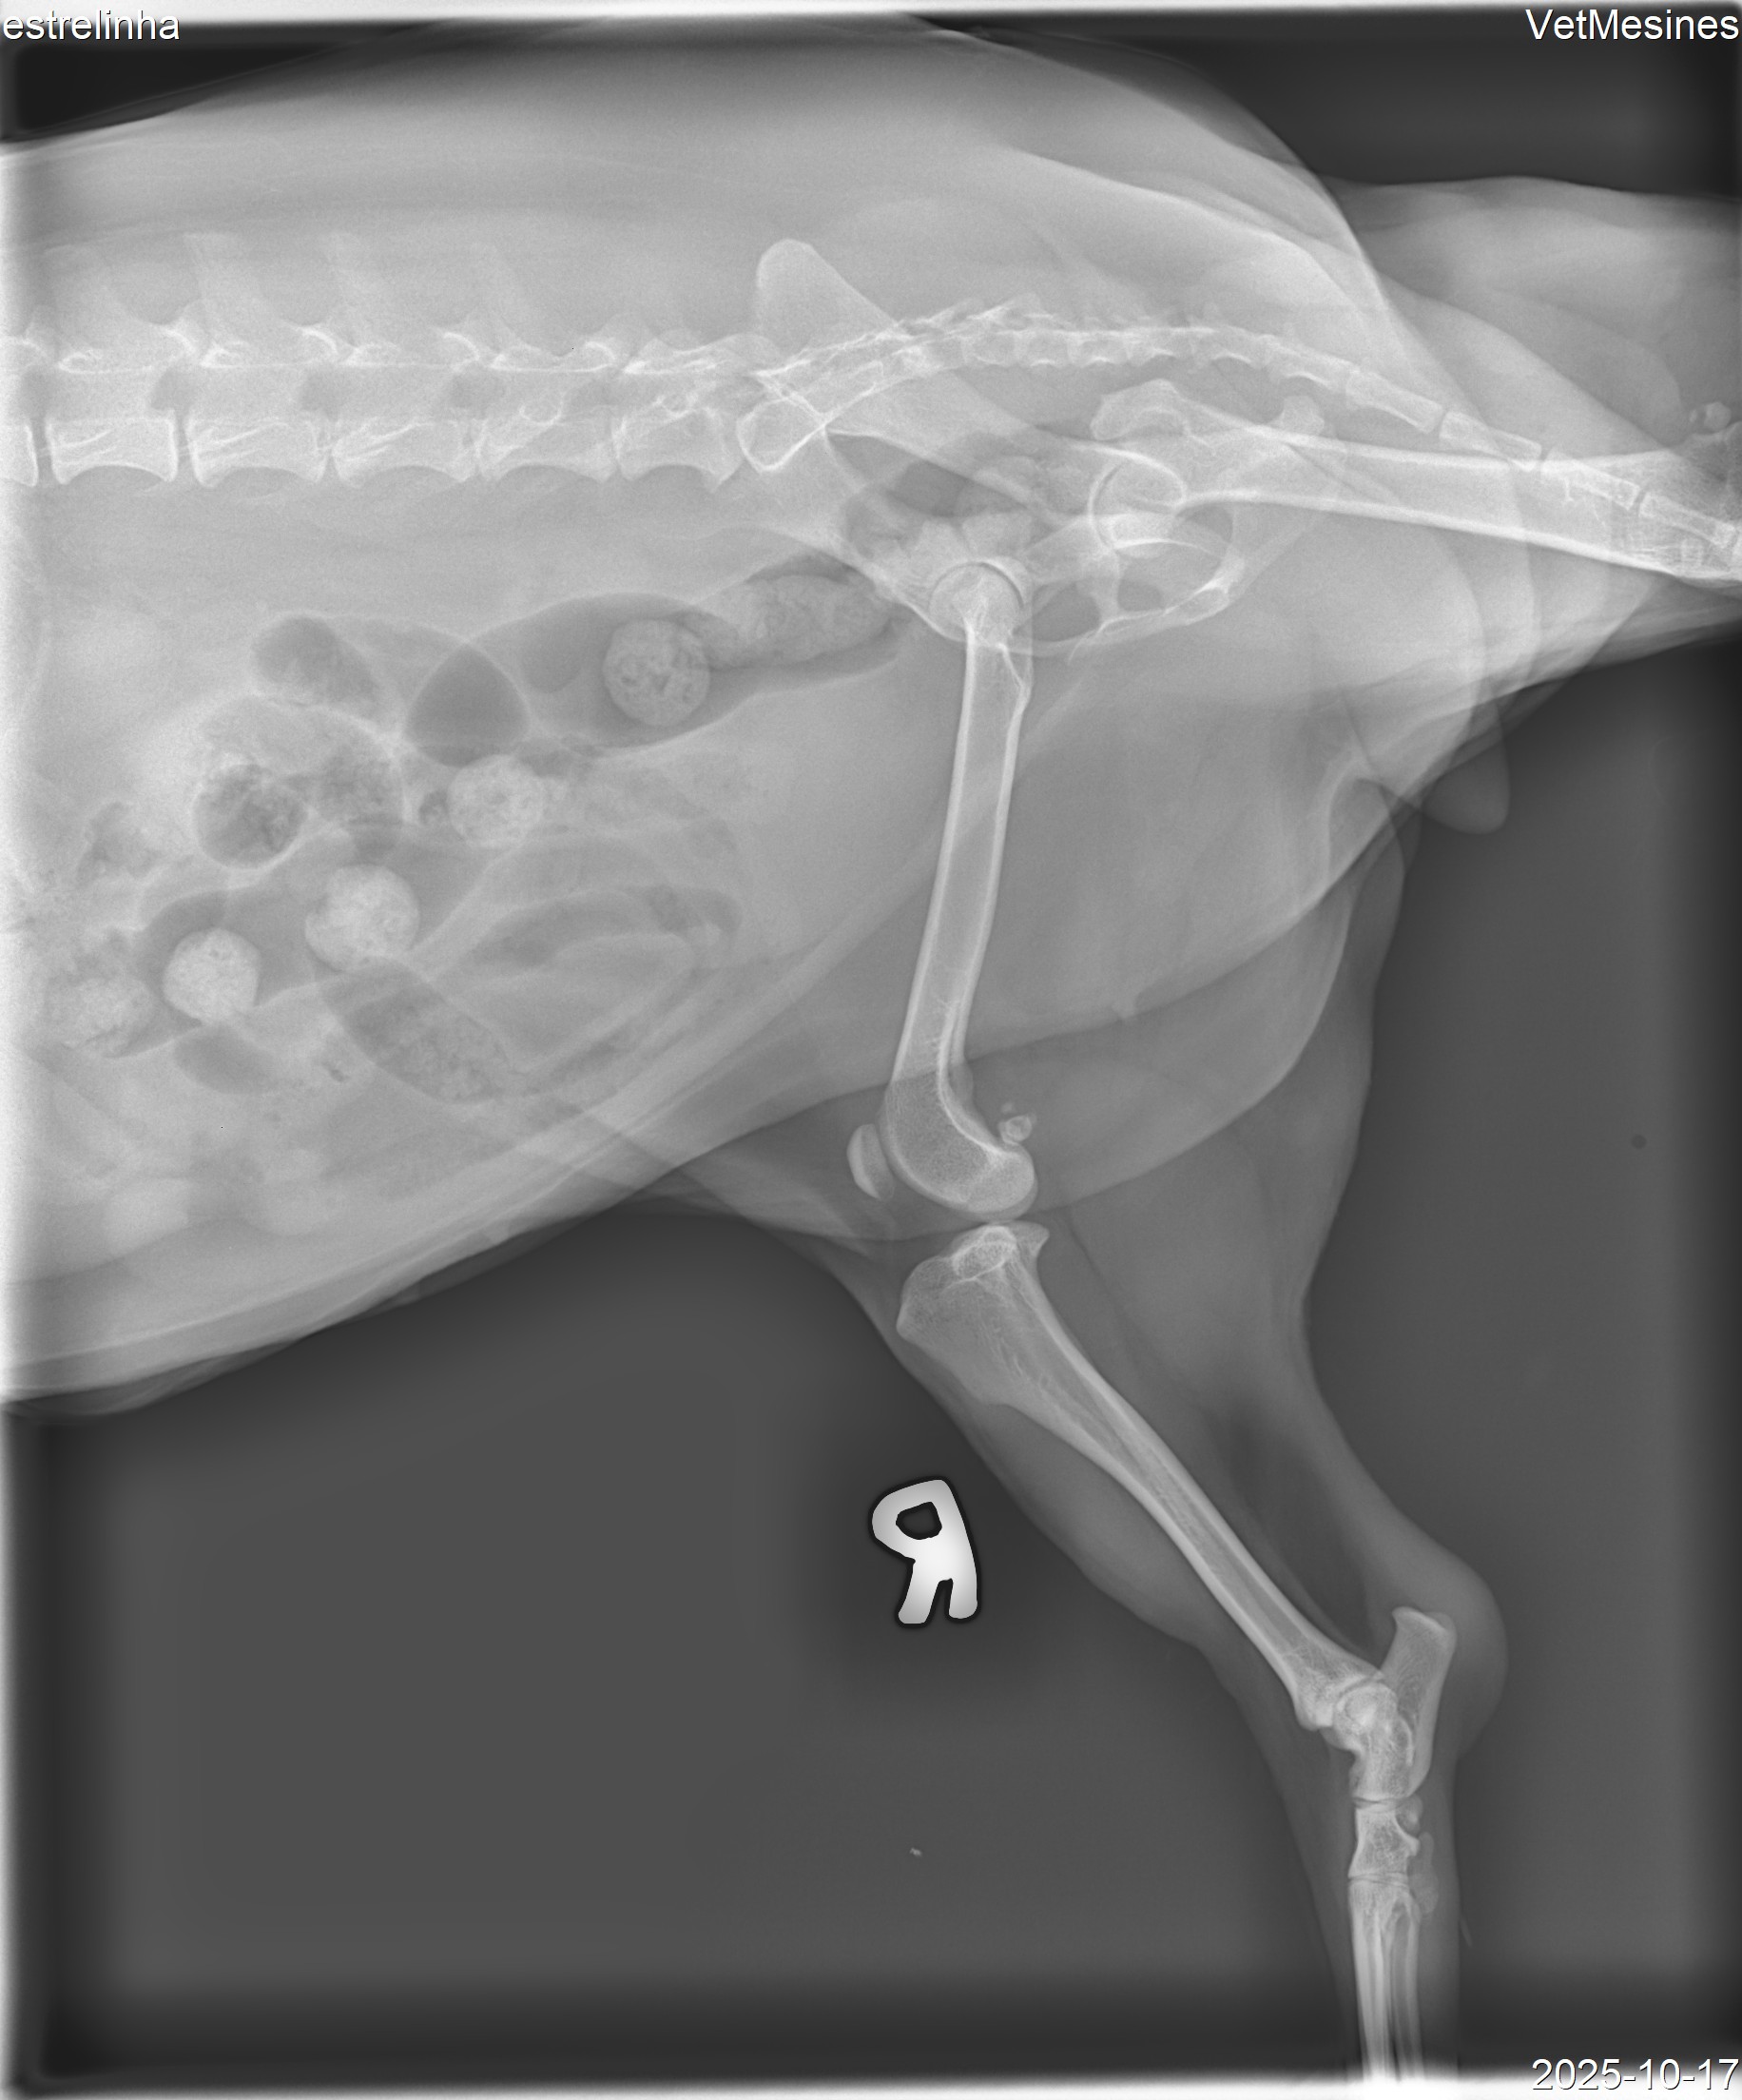

A pobre Estrelinha estava a viver uma vida feliz como cadela mais velha com a sua família quando, de repente, teve dores terríveis e não conseguia colocar a pata no chão. O veterinário diagnosticou uma rutura do ligamento cruzado, e ela precisava de uma operação com pinos e uma placa para ajudar na dor e mobilidade e dar força à pata onde estava a lesão. Assim, pagámos 162,83 euros por alguns testes para garantir que ela estava o mais saudável possível, depois pagámos 1190 euros pela sua operação, que incluiu a remoção de uma hérnia enquanto era feita a operação da pata, permitindo que voltasse à sua vida feliz e saudável.

Raio-X da Estrelinha